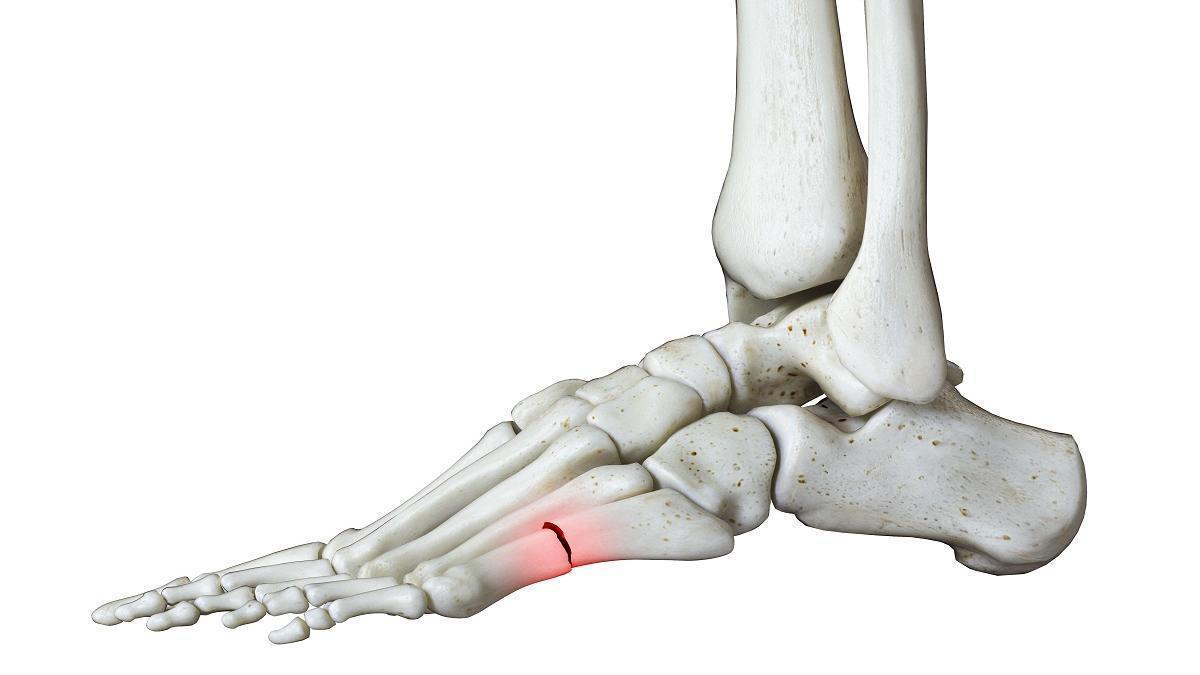

Com ataca l'estrès als peus? Així es preveu i es tracta "la fractura del recluta"

Aquest tipus de lesions solen produir-se en iniciar l'activitat esportiva o laboral de manera brusca i excessiva

Fractura del recluta

“Al llarg dels anys, aquest tipus de fractura ha rebut molts noms com “la fractura del recluta” o la “fractura del marxador”, perquè és molt comú en soldats.

Però realment són fractures per estrès o per sobrecàrrega. I com explica Jorge Escoto, podòleg i membre de la junta directiva de l'ICOPCV:

“Si bé, poden donar-se en qualsevol os, però les més comunes són les que es donen al segon i tercer metatarsià”.